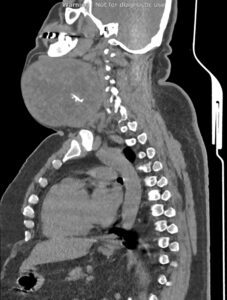

در سی تی اسکن اسپیرال از گردن ، ریه و مدیاستن با و بدون تزریق (مولتی دیدکتور 16 با مقاطع ظریف و بازسازی های ساژیتال و کرونال):

بیمار آقای 44 ساله با توده گردنی جهت بررسی بیشتر، مراجعه نمودند:

تصویر توده بزرگ به ابعاد 118x133mm در پلن آگزیال و دیامتر کرانیو کودال 126mm در سمت چپ گردن با نمای هتروژن و کلسیفیکاسیون Coarse مرکزی رویت می شود. به نظرمنشا توده ذکر شده از لوب چپ تیروئید می باشد. گسترش فوقانی توده تا سطح مهره دوم گردنی و زیر زاویه مندیبل و گسترش تحتانی آن تا ناحیه سوپراکلاویکولار بدون گسترش اینتراتوراسیک رویت می شود.

اثر فشاری توده ذکر شده به تراشه با انحراف آن به سمت مقابل رویت می شود.

اثر فشاری توده ذکر شده به ورید ژوگولارداخلی و CCA با جابه جایی خلفی و به SCM با جابه جایی خلفی لترال آن مشهود است.

مجموع یافته ها مطرح کننده توده تیروئید با اثرات ذکر شده می باشد.